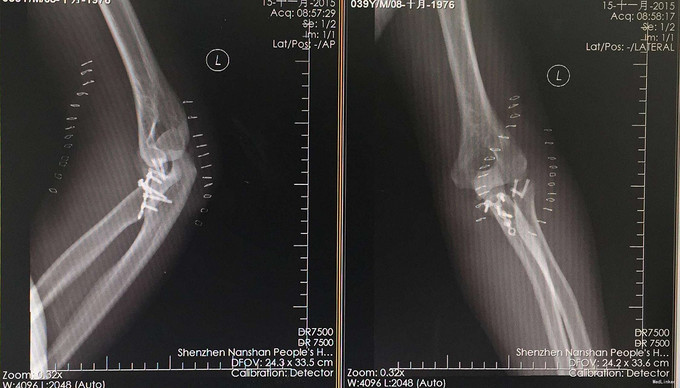

完善检查,行左尺骨鹰嘴冠突骨折+左桡骨小头骨折切开复位内固定术

术后2周复诊,伸直130°,屈曲80°。 请教各路大侠,这类患者功能锻炼如何指导,因为患者对疼痛恐惧,不配合。